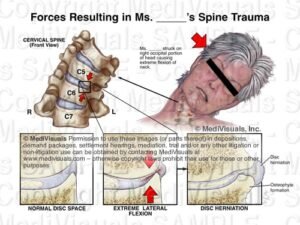

Шиповете във врата, известни още като костни шипове (остеофити), представляват костни образувания, които се развиват по ръбовете на прешлените в шийната част на гръбначния стълб.

В много случаи шиповете не причиняват симптоми. Когато обаче започнат да притискат нервни структури или да ограничават движението, могат да доведат до болка във врата, скованост и изтръпване.

С течение на времето организмът може да образува костна тъкан като реакция на нестабилност или натоварване, което води до появата на остеофити.

Симптомите често зависят от това дали има притискане на нервни структури.

• притискане на нервни структури

Оперативно лечение може да се обсъжда само в определени случаи, когато има значително притискане на нервните структури или сериозни неврологични симптоми.